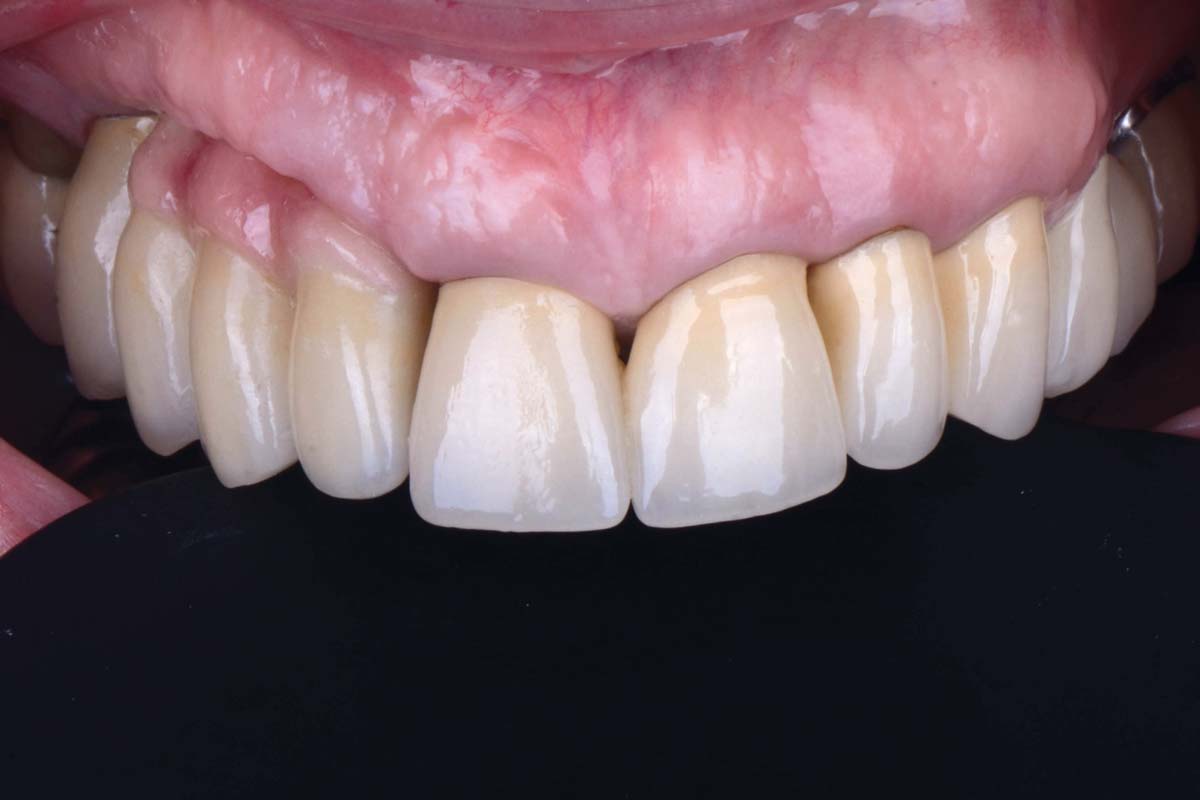

Bone defect in area 11-21 due to two lost implants (periimplantitis) after 15 years of function